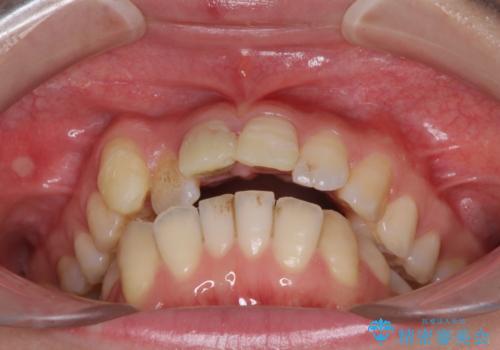

転んで前歯が欠けた 折れた前歯をきっかけに矯正治療で歯列をきれいに整える

- 転倒により前歯の一部が欠けてしまったとのことで来院された患者様です。

神経が保存できる歯、神経を除去しなければならない歯、抜歯が必要な歯があり、ブリッジやインプラントなどによる治療を提案しました。

元々歯並びが気になっていたとのことで、前歯の治療を行うことを契機に矯正治療も行うこととしました。

本来であれば積極的に小臼歯を抜歯して口元を下げても良いのですが、前歯を1本抜歯しないといけなくなったため、非抜歯矯正をインビザラインを用いて行うこととしました。